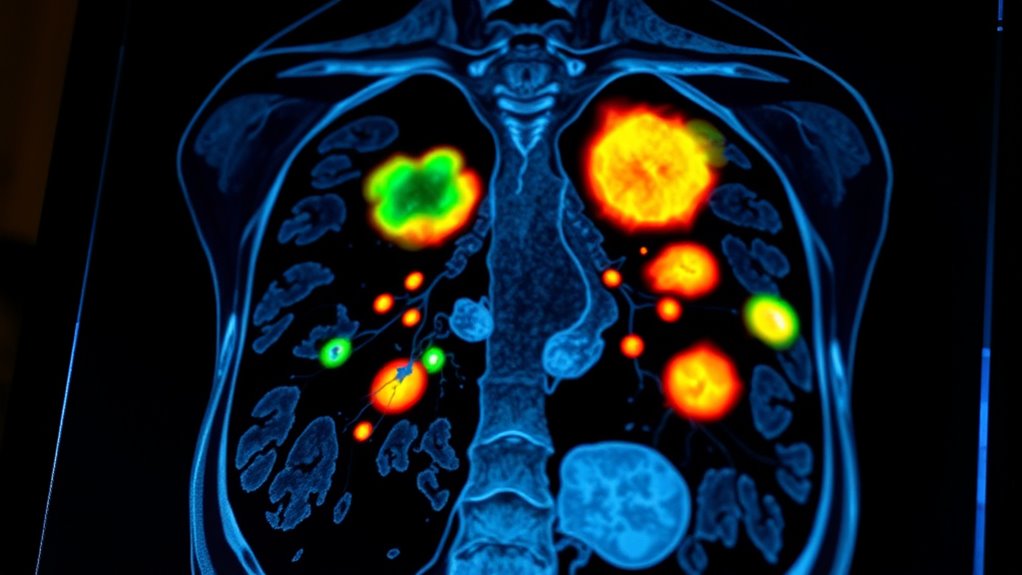

CT- und PET-CT-Scans sind entscheidende bildgebende Verfahren, die Ihnen helfen, Tumormetastasen zu erkennen, indem sie detaillierte strukturelle Bilder mit funktionellen metabolischen Daten kombinieren. Besonders PET-CT bietet hohe Sensitivität und Spezifität, was es Ihnen ermöglicht, kleine oder versteckte Metastasen zu identifizieren, die andere Methoden möglicherweise übersehen. Diese Scans verbessern die Stadieneinschätzung und leiten die Behandlungsplanung. Um zu erfahren, wie diese fortschrittlichen Techniken zusammenarbeiten und welche Vorteile sie bieten, erkunden Sie weiterhin.

Bildgebungstechniken spielen eine wesentliche Rolle bei der Erkennung und Stadieneinteilung von Krebs, indem sie wichtige Informationen über den Tumorort, die Größe und die Ausbreitung liefern. Diese Methoden helfen Ihnen, Tumoren zu visualisieren, ihr Ausmaß zu bestimmen und Behandlungsentscheidungen zu lenken. Konventionelle Bildgebungsverfahren wie CT-Scans, Ultraschall und Röntgen bieten detaillierte strukturelle Informationen, heben die Tumorgröße und anatomische Beziehungen hervor. PET-Scans hingegen erkennen metabolische Aktivität, indem sie die Aufnahme von Radiotracern verfolgen, was aktive Krebszellen aufdecken kann, die von anderen Techniken oft übersehen werden. Die Kombination von funktionalen und strukturellen Daten, wie bei PET/CT, erhöht die Genauigkeit, insbesondere bei der Identifizierung von Metastasen. Dieses Zusammenspiel ermöglicht eine präzise Lokalisierung der Tumoren, eine bessere Unterscheidung zwischen benignen und malignen Läsionen und eine verbesserte Stadieneinteilung. Zusammen bilden diese Bildgebungsmodalitäten einen ganzheitlichen Ansatz zum effektiven Verständnis und Management von Krebs.

PET/CT kombiniert nahtlos funktionale und strukturelle Informationen und bietet einen umfassenden Blick auf Krebs. PET zeigt, wie aktiv der Tumor ist, indem es die Aufnahme von Radiotracern nachweist, was die metabolischen Prozesse widerspiegelt. Gleichzeitig zeigt CT die genaue Lage und Größe des Tumors und bietet detaillierte Anatomie. Die Kombination dieser beiden Verfahren ermöglicht eine präzise Bestimmung von Tumoraktivität und -struktur gleichzeitig. Diese Fusion verbessert die Biopsie-Targeting und hilft dabei, benigne von malignen Läsionen zu unterscheiden, wenn andere bildgebende Verfahren an ihre Grenzen stoßen. Sie können kleine oder nekrotische Tumoren besser lokalisieren, was die Behandlungsplanung verbessert. Die folgende Tabelle hebt die wichtigsten Aspekte dieser Integration hervor: